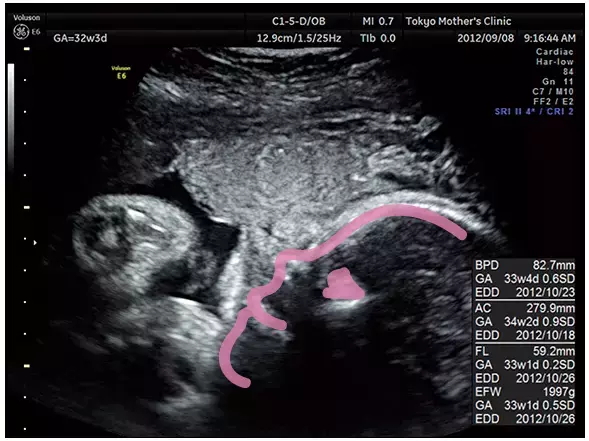

妊娠32週のエコー写真

ふっくら赤ちゃん 表情豊かに

皮下脂肪が増え、見た目的には新生児と変わらない体型に近づいてきます。顔もふっくらして、なんとなく表情が感じられ、ますます対面が楽しみになるでしょう。赤ちゃんが逆子になっている場合、向きを直す体操をすすめられることもあります。胎盤の位置によっては帝王切開になる場合もあるので、それも確認します。

ちょっと口角があがって、まるで笑っているような表情の横顔が見えます。